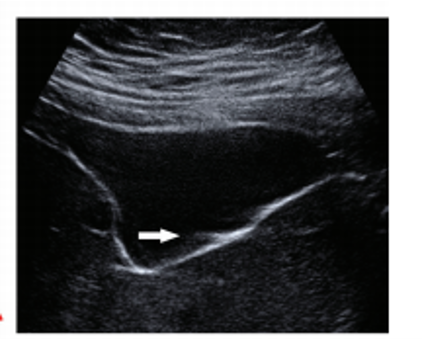

why do you get a tapering triangle in comet tail artifact?

comet tail artifact is a form of reverberation, but the two parallel highly reflective surfaces are closer together –> sequential echoes are closely spaced

spce between reflectors may be < SPL (minimal distance needed for axial res)

Reason you see a triangle and not a square: later echoes get attenuated and have decreased amplitutde. Decreased amplitude is manifested on the displayu as decreased width. So you get a tapering triangle